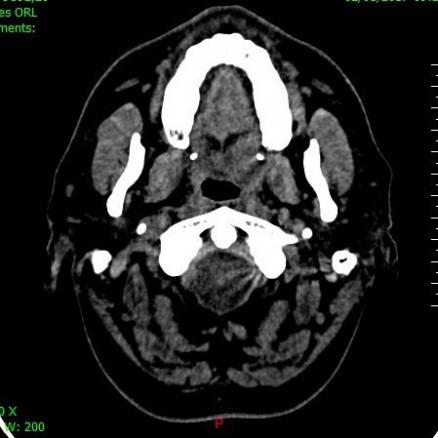

Adénocarcinome polymorphe de bas grade

Collection P. Frances